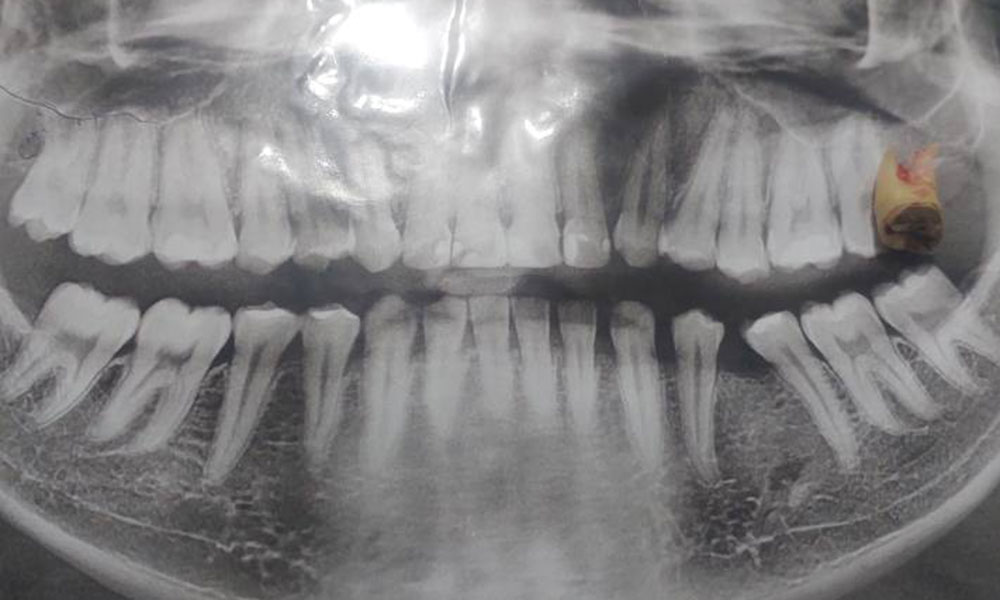

4. دندانهای آسیای بزرگ (Molars)

- تعداد: ۱۲ عدد (۳ عدد در هر نیمفک)

- موقعیت: عقبترین قسمت دهان

- کارکرد: آسیاب کامل غذا

- مهمترین: دندان آسیای اول یا دندان ۶ سالگی (اولین دندان دائمی)

دندان عقل (Wisdom Tooth)

آخرین دندانهای آسیای بزرگ که در سنین ۱۶ تا ۲۵ سالگی رویش پیدا میکنند. معمولاً ۴ عدد هستند، اما ممکن است کمتر یا بیشتر یا حتی اصلاً رشد نکنند.

مشکلات رایج:

- نهفتگی کامل یا نیمه

- فشار به دندان کناری

- التهاب و عفونت لثه

- نیاز به جراحی برای کشیدن